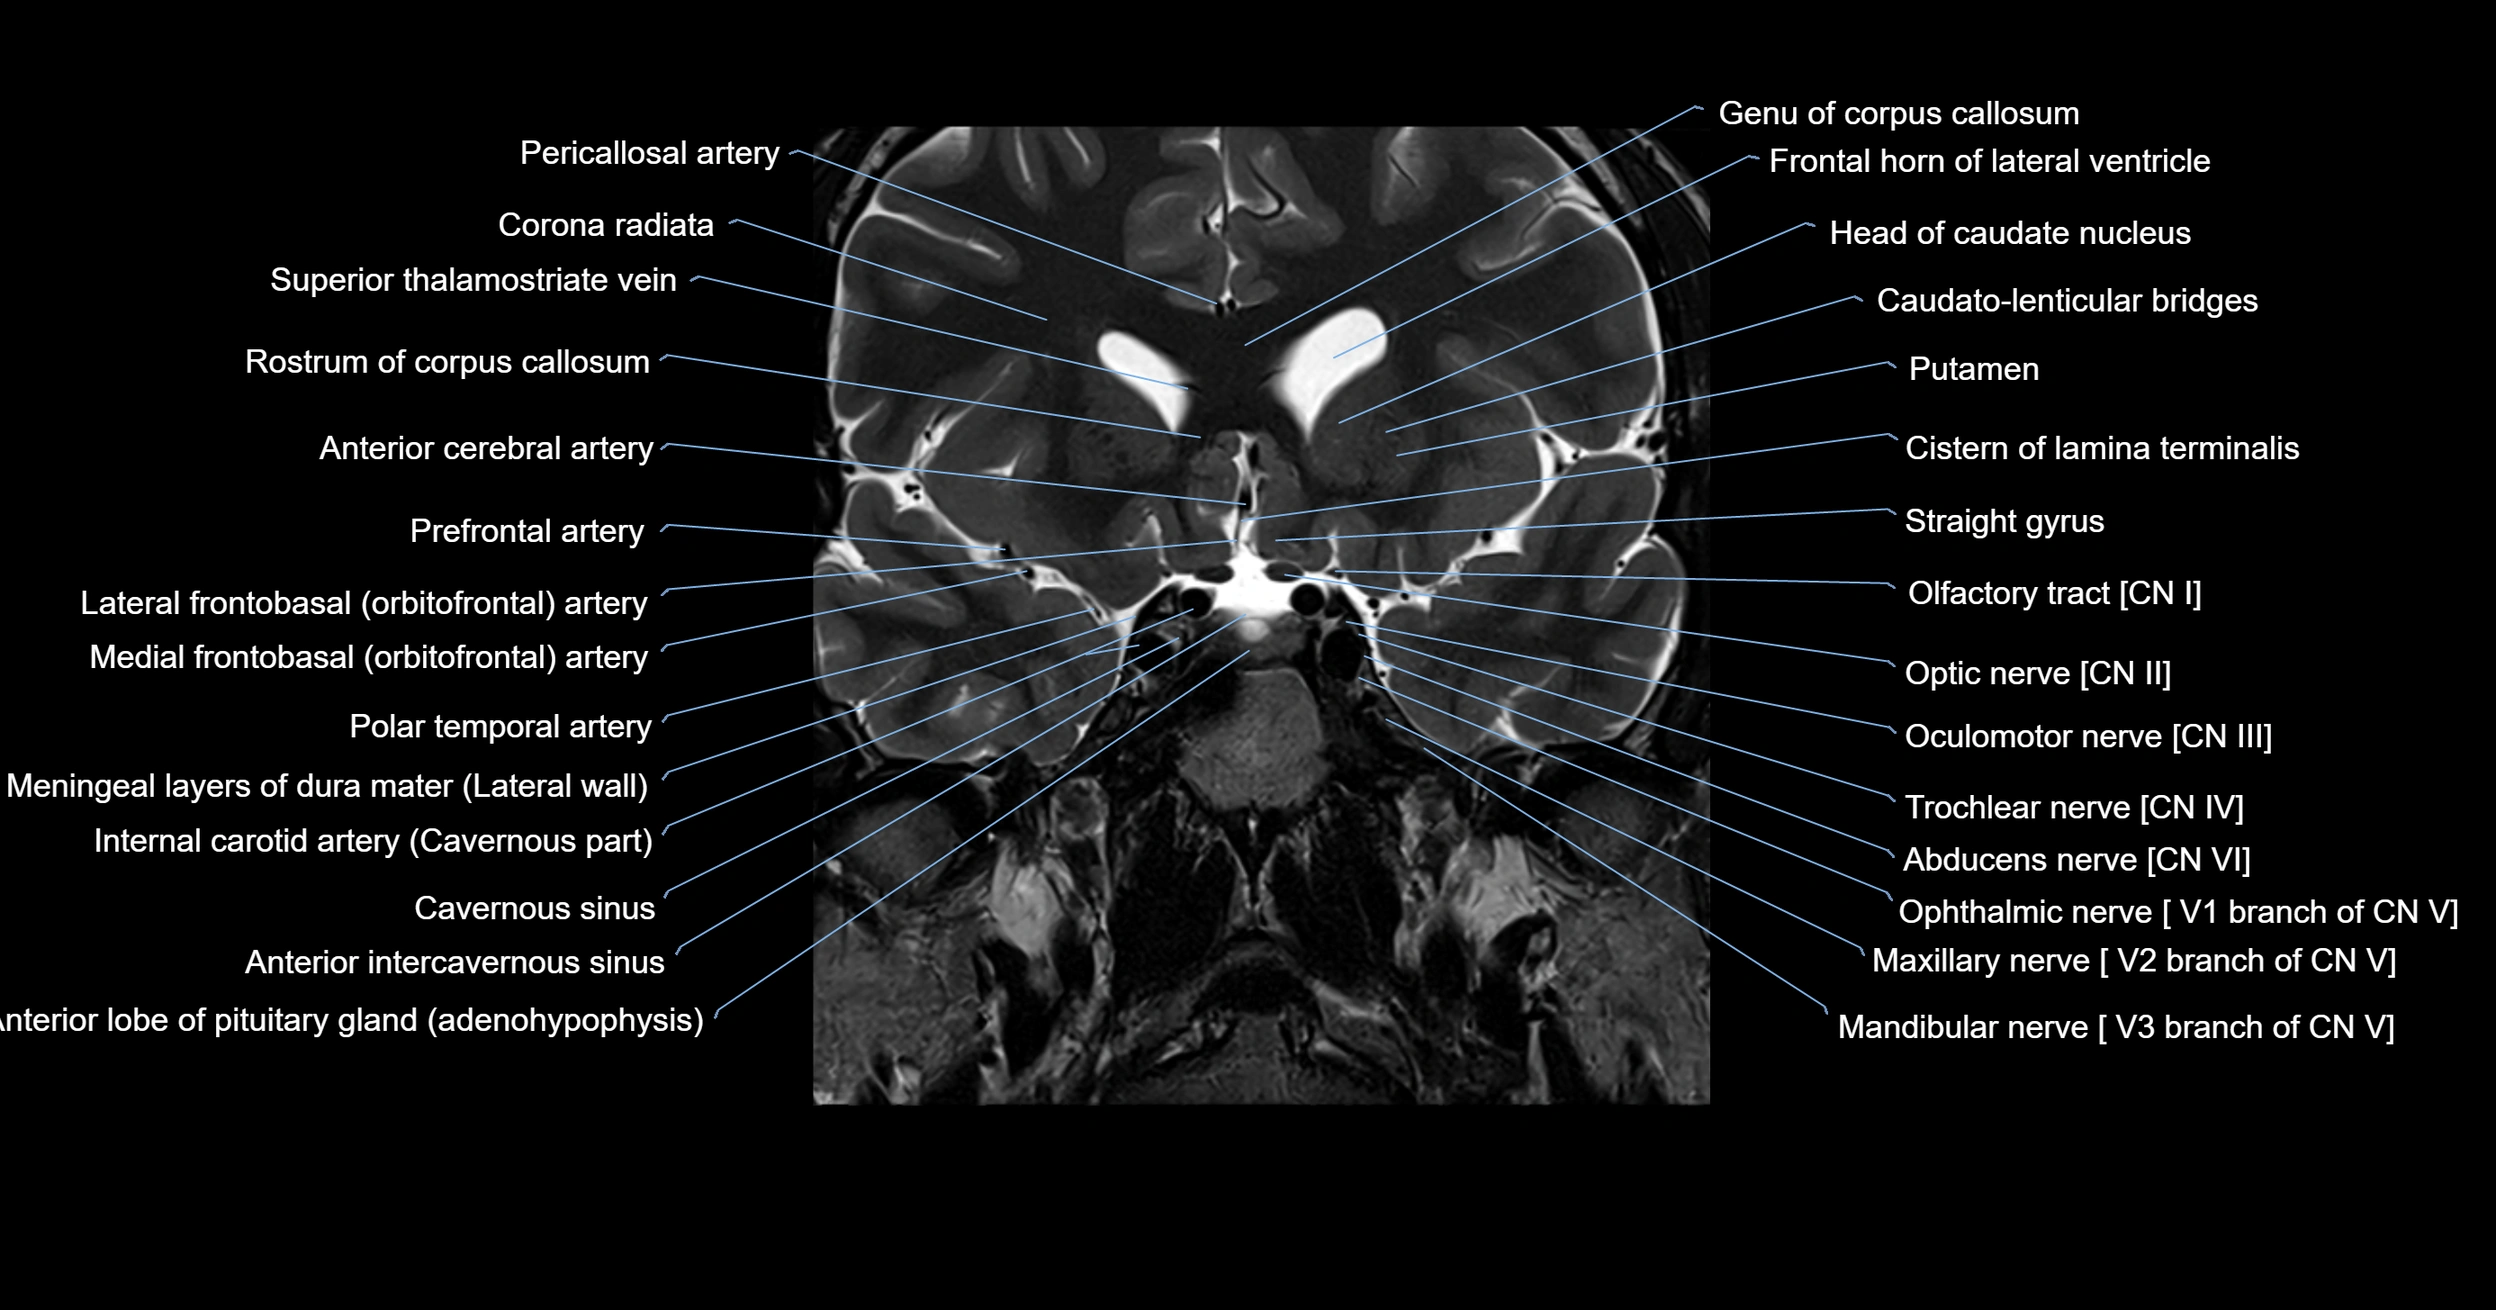

MRI images